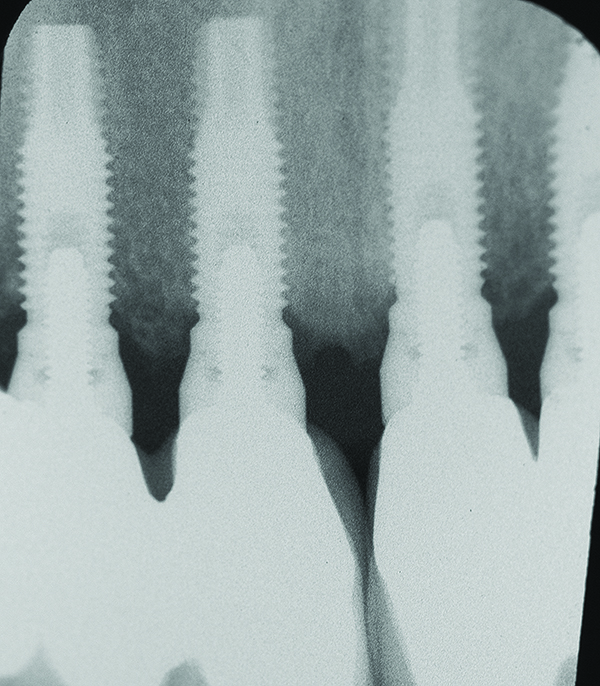

Fig 1 through Fig 6. Periapical radiographs of a 52-year-old man who received a fixed porcelain-fused-to-metal reconstruction supported by abutments attached to externally hexed dental implants. Fig 1 through Fig 3 are at initial prosthesis placement: maxillary right (Fig 1), textured surfaced threaded titanium implants at site Nos. 2, 4, and 6; maxillary anterior (Fig 2), implants at site Nos. 7 through 9; maxillary left (Fig 3), implants at site Nos. 12 and 14. Fig 4 through Fig 6 are 10 years post-insertion of the prosthesis: maxillary right (Fig 4), maxillary anterior (Fig 5), and maxillary left (Fig 6). Note minimal to no bone loss radiographically around the implants 10 years post-insertion of prosthesis.

Figure 5

Fig 7 through Fig 14. Periapical radiographs of a 62-year-old woman who received a fixed porcelain-fused-to-metal reconstruction supported by abutments by internally connected dental implants. Fig 7 through Fig 10 are at initial prosthesis placement: mandibular site Nos. 30 and 29 (Fig 7); mandibular site Nos. 26, 25, and 23 (Fig 8); mandibular site Nos. 23 and 21 (Fig 9); mandibular site Nos. 21 through 19 (Fig 10). Fig 11 through Fig 14 are 11 years later (2013) and show excellent preservation of the vertical bone levels around the implants: mandibular site Nos. 30 and 29 (Fig 11); mandibular site Nos. 26 and 25 (Fig 12); mandibular site Nos. 25 and 23 (Fig 13); mandibular site Nos. 20 and 19 (Fig 14). It is interesting to note that in the mandibular right posterior quadrant there is a matched pair, ie, an external hex dental implant (No. 30) adjacent to an internally connected dental implant (No. 29). The bone levels around each of these designs are well-preserved at the 11-year follow-up.

Figure 11